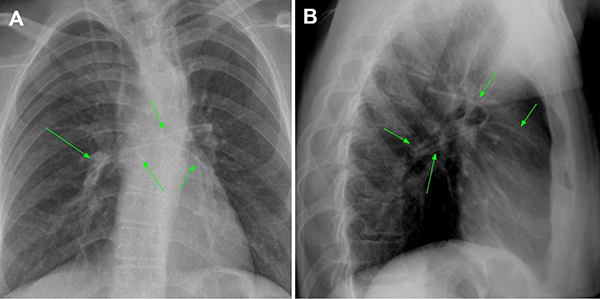

Tras 2 meses, la paciente volvió a consultar en guardia por náuseas, cefalea bifrontal con irradiación holocraneana de intensidad moderada y vómitos. Al examen físico se constató limitación de la mirada superior y colección líquida sobre herida craneal de derivación. Se realizó TC de cerebro con evidencia de ventriculomegalia y desconexión de catéter distal a la válvula (Figura 1). El estudio radiográfico reveló migración caudal del segmento distal del catéter al corazón (Figura 2). El segmento migrado fue rescatado mediante un abordaje endovascular transfemoral, en el cual se enroscó el catéter migrado con un catéter pigtail y se lo desplazó hasta la vena ilíaca primitiva izquierda para luego ser capturado a nivel ilíaco con un lazo trilobulado (Figura 3).

Figura 1. A y B. Corte axial y sagital de TC de cerebro evidenciando marcada hidrocefalia supratentorial. C. Reconstrucción 3D de dicha tomografía, se observa desconexión del catéter distal (flecha verde). Aclaración: sobre mastoides izquierda se evidencia catéter calcificado de válvula previa abandonada. D. Imagen intraquirúrgica con evidencia de desconexión de segmento distal.